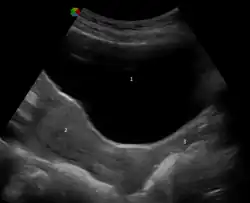

Ultrasonograph depicting urinary bladder at the top, above the uterus to its bottom-left and vagina to its bottom-right

An ultrasound showing the urinary bladder (1), uterus (2), and vagina (3)